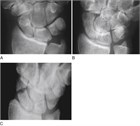

臨床像

舟状骨骨折は14~40歳に好発し,手関節を伸展した状態で手をついて転倒(FOOSH)し,関節可動域(ROM)の減少と手関節(特に橈側の背側)に強い痛みを訴える.身体診察では,変形や斑状出血はみられないが,動作や触診で疼痛を認め,しばしば腫脹もみられる.腫脹は特に解剖学的嗅ぎタバコ入れ(母指を伸展した際に,長母指外転筋と短母指伸筋の腱の間にある,手関節の橈側にみられる窪み.127.1)でみられる.疼痛は軽度のこともあるが,握ったり掴んだりすると悪化する.